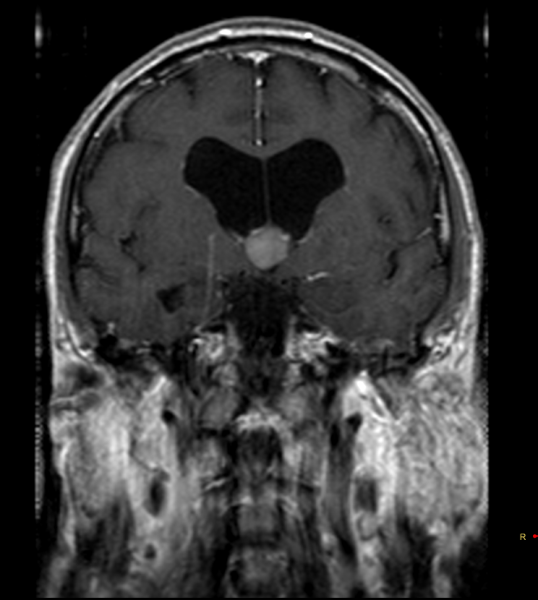

Ασθενής 63 ετών, προσέρχεται λόγω αναφερόμενων από το οικείο περιβάλλον διαταραχών βάδισης, πρόσφατης μνήμης και προσωπικότητας, συμτωματολογία αρχόμενη προ τριετίας.Υπεβλήθη σε μαγνητική τομογραφία εγκεφάλου η οποία ανέδειξε κυστική εξεργασία στο κατώτερο τμήμα της τρίτης κοιλίας (18x16x14mm), χαμηλού σήματος στις Τ2 ακολουθίες και υψηλού σήματος στις Τ1 (ως επί κολλοειδούς κύστης). Ο ασθενής αντιμετωπίστηκε αρχικά συντηρητικά, υπό παρακολούθηση με ετήσιο έλεγχο με μαγνητική τομογραφία. Από το περιβάλλον αναφέρεται προοδευτικά επιδείνούμενη συμτωματολογία κατά το τελευταίο εξάμηνο, για την οποία και αποφασίστηκε χειρουργική αντιμετώπιση.

Προεγχειρητικός απεικονιστικός έλεγχος